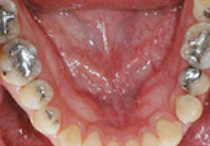

BEFORE

AFTER